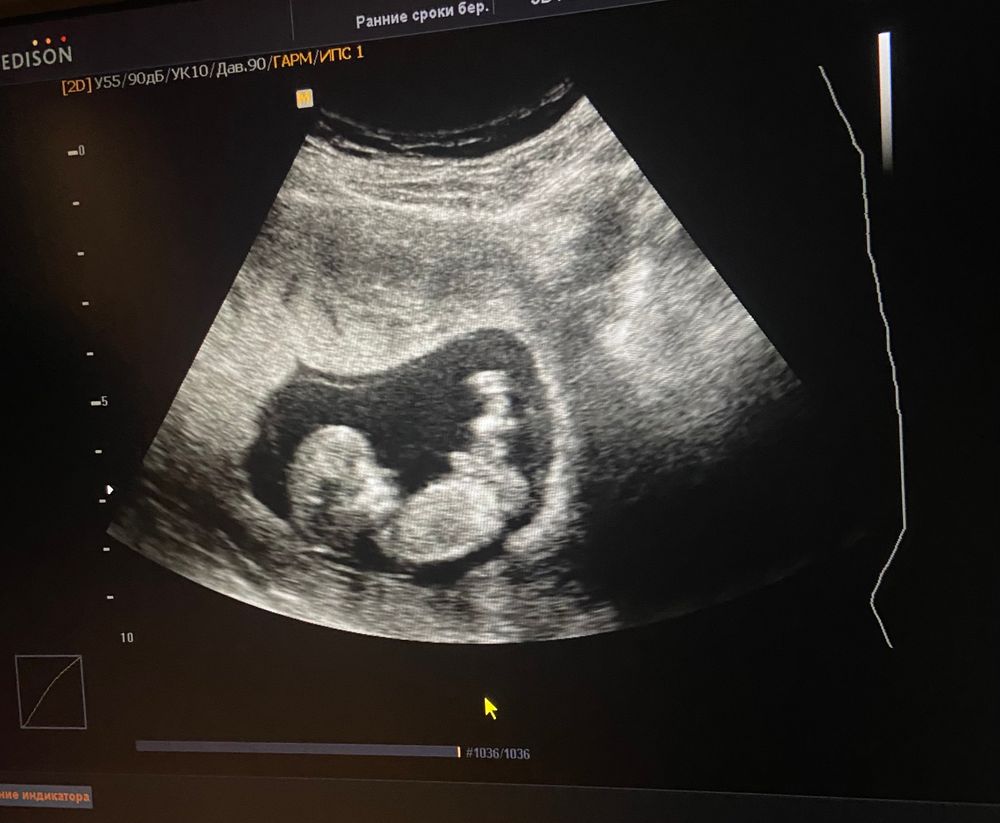

Девочки, отставить панику, все в порядке нижний край хориона перекрывает внутренний зев, шейка высоко 40,5 мм сказали такое может быть выделений больше нет прописали дюф и транексам, но я ещё своей г позвоню спрошу точно это все надо пить? так как и так утрик 600 у меня Такие дела вообщем, я паникёр, кроха растёт по узи срок больше даже 12 недель и три дня) Изображение